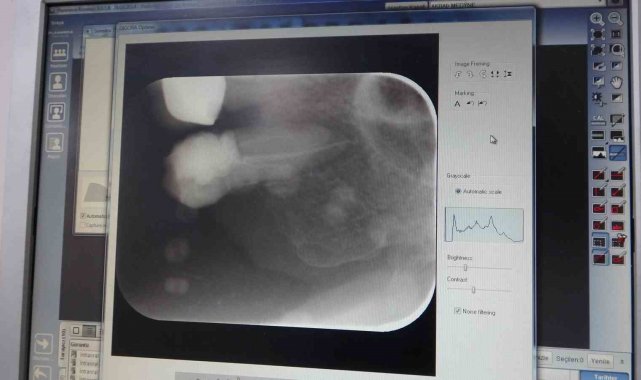

İnönü Üniversitesi Diş Hekimliği Fakültesi Dekanı ve Endodonti Uzmanı Prof. Dr. Neslihan Şimşek, Diş Hekimliği Fakültesi'ne geçtiğimiz yıl 303 bin hastanın başvuru bulunduğunu belirterek yaklaşık 11 bin hastaya ise kanal tedavisi uygulandığını kaydetti.

2024 yılında 303 bin hastanın başvuru yaptığını vurgulayan Şimşek, "2024 yılında 303 bin hasta başvuru yaparken, bunlardan yaklaşık 11 bin hastaya kanal tedavisi uygulandı" ifadelerini kullandı. Şimşek, fakültede toplamda 12 milyon 250 binin üzerinde diş tedavisi gerçekleştirildiğini de söyledi.

Tedavi ihtiyaçlarının bir çok nedeni olduğunu belirten Dr. Şimşek, "Kanal tedavisinin endikasyonları birden fazladır. Diş çok ağrıdığı zaman veya bir travma ile kırıldığı zaman, protetik işlemler öncesi gibi durumlarda kanal tedavi uygulanabilir. Tedavi sonrasında ise anestezinin etkisi geçene kadar kullanılmamasını ve tedavi uygulanan dişin test edilmemesini tavsiye ediyoruz" diye konuştu.